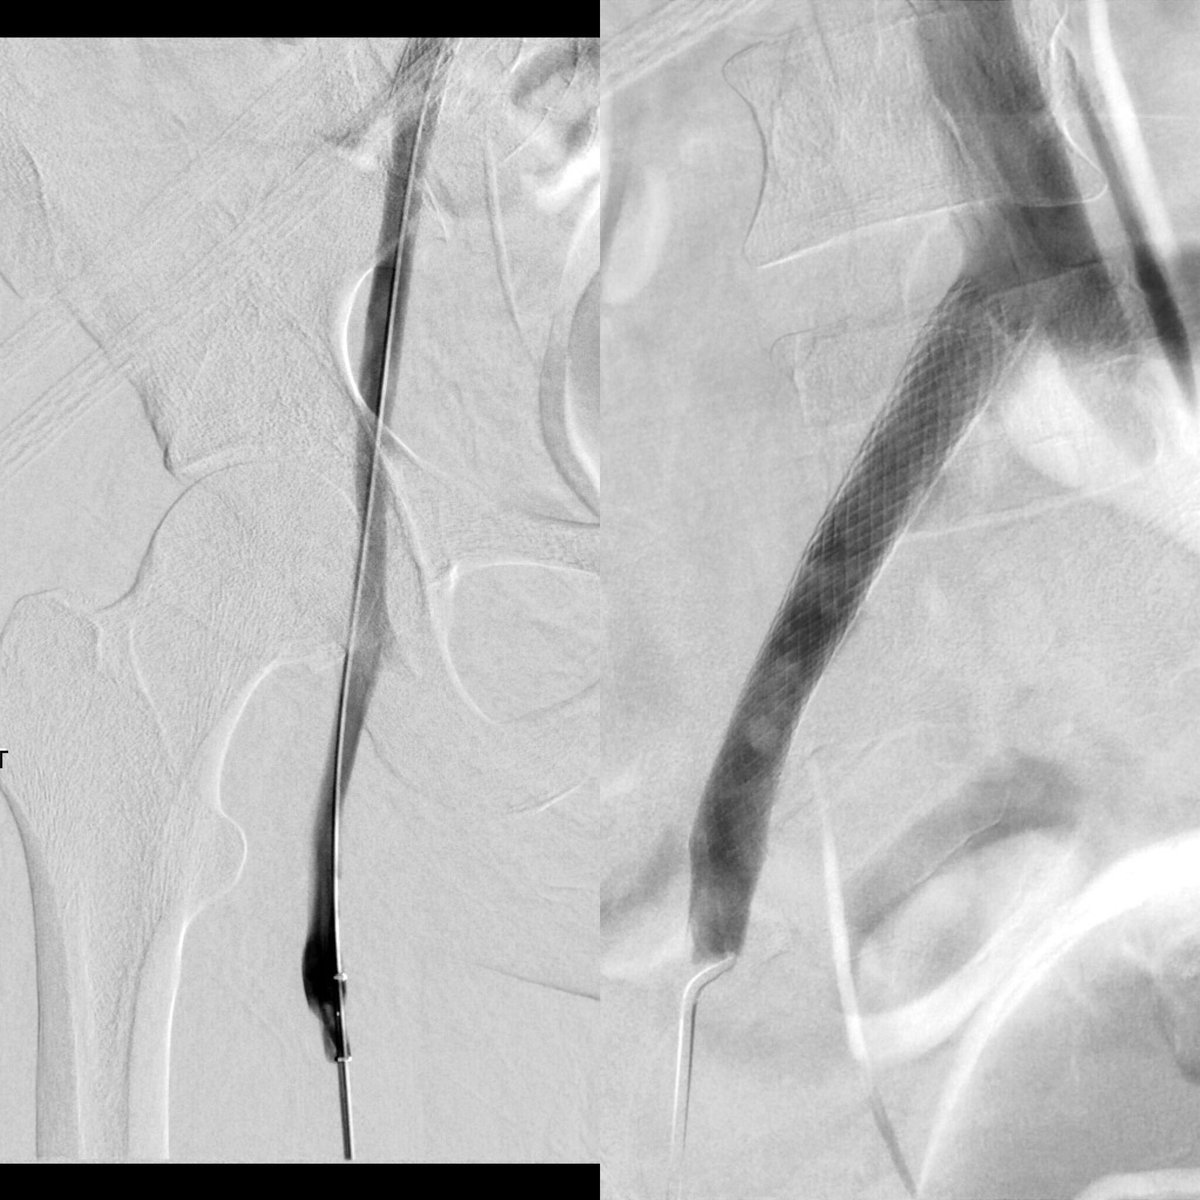

67 yo w/solitary 4cm HCC. Not an operative candidate 2/2 comorbidities and liver function. y90 ablative dose delivered via single arterial supply. Tumor kill dose confirmed with post-y90 PET. albanyir.com/iocase11 #IRad #WithoutAScalpel #IO @SIRRFS @JVIRmedia